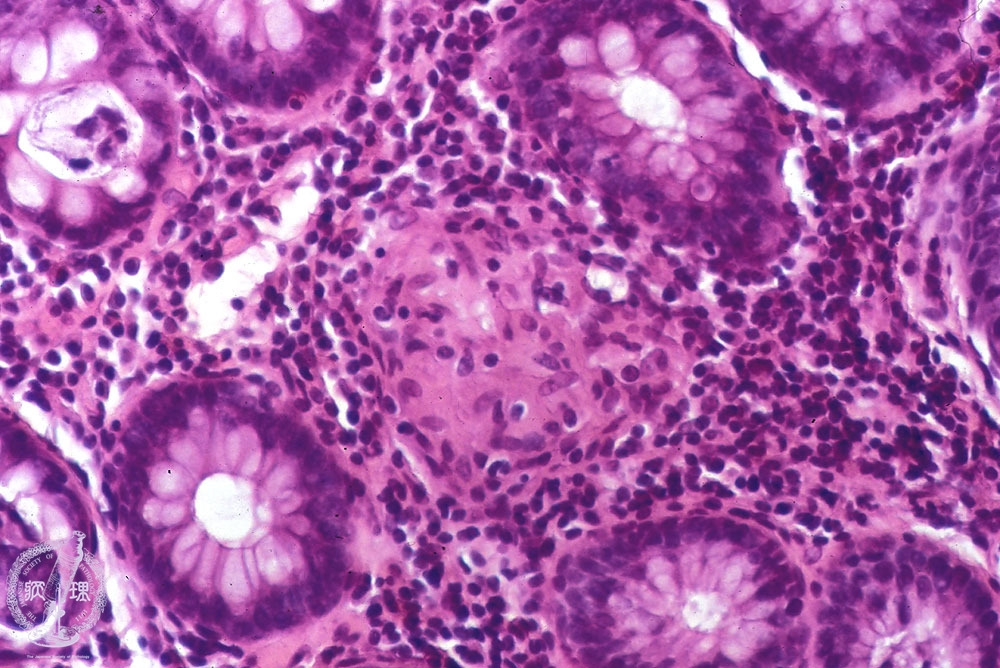

이 크론병 의 가장 큰 특징은 염증이 연속적으로 퍼지는 것이 아니라 정상 부위와 병변이 섞여 나타나는 점이며, 장 벽의 점막층뿐 아니라 근육층, 장막층까지 깊게 침범할 수 있다는 점입니다. 이러한 특성 때문에 협착, 누공, 농양과 같은 구조적 합병증으로 이어질 위험이 높습니다. 크론병은 완치 개념보다는 관해와 재발을 반복하는 만성 질환으로 분류되며, 장기적인 관리와 생활 조절이 핵심이 됩니다.

면역 체계 이상

정상적인 면역 체계는 장내 세균과 공존하면서 외부 병원체만 선택적으로 방어합니다. 그러나 크론병 환자의 경우 면역 반응이 과도하게 활성화되어 정상 장 조직을 공격하게 됩니다. 이로 인해 만성적인 염증 반응이 지속되고, 장 벽 손상이 반복되면서 증상이 악화됩니다. 이러한 면역 이상은 크론병을 자가면역 질환 성격을 가진 질환으로 분류하는 근거가 됩니다.